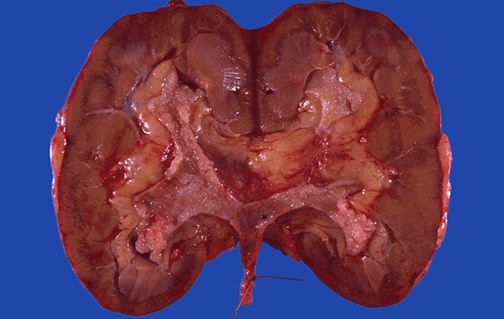

The kidney has been bivalved to show the collecting system. A soft pink papillary mass is attached to the urothelium and fills part of the collecting system.